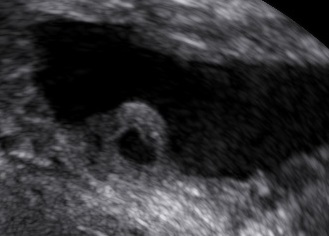

On ultrasound the ureterocele within the bladder appears like a cyst within a cyst. During live examination the ureterocele can be seen to inflate and deflate.